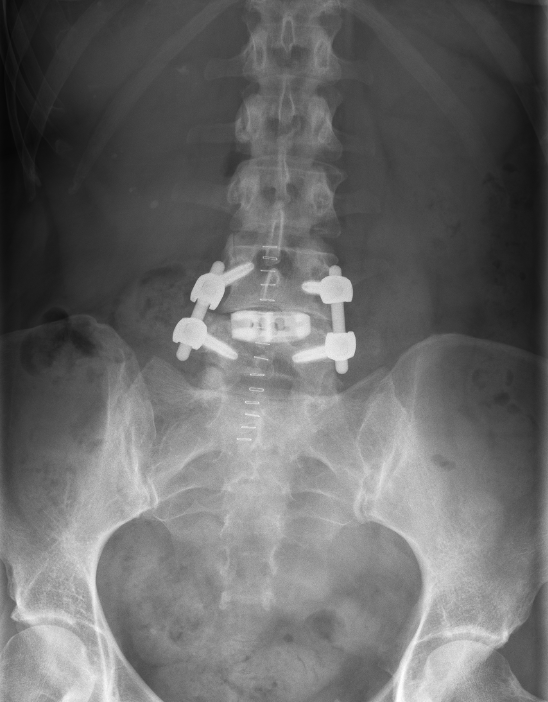

TLIF Röntgen

AP Röntgenbild eines Patienten wenige Tage nach Durchführung eines TLIF LWK4/5.